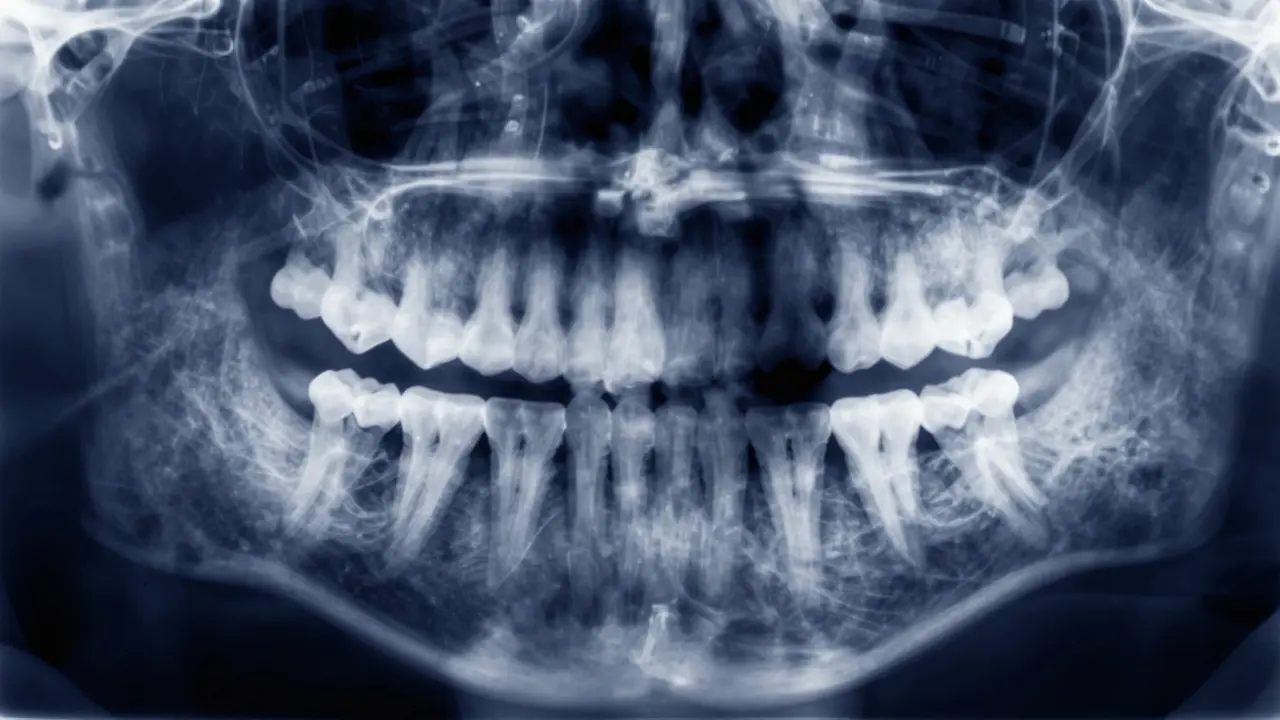

Rentgenový snímek zubů znázornující skrytý kaz v mezeře mezi moláry.

Rentgen je v zubařství naprosto klíčový. Zatímco zrcátko vidí jen povrch, Rentgen zubů (RTG) umožňuje nahlédnout dovnitř. Existují dva hlavní typy snímků, které zubař používá při hledání kazů. Za prvních jsou tzv. kousací snímky (bitewing). Zubař vám do úst vloží malý film nebo digitální senzor a vy ho kousnete. Tento snímky jsou perfektní pro detekci těch zmiňovaných kazů v mezerách mezi zuby. Na snímku vypadá zdravý zub jasně bíle, zatímco karies se jeví jako tmavší, šedá nebo černá oblast, protože bakterie vyjedly minerály a rentgenové paprsky tudy procházejí snadněji. Pak jsou panoramatické snímky, které zachycují celý čelistní oblouk. Ty sice nejsou tak detailní pro malé kazy, ale jsou skvělé pro odhalení problémů u kořenů, zapálených zubů nebo sledování růstu zubů u dětí.